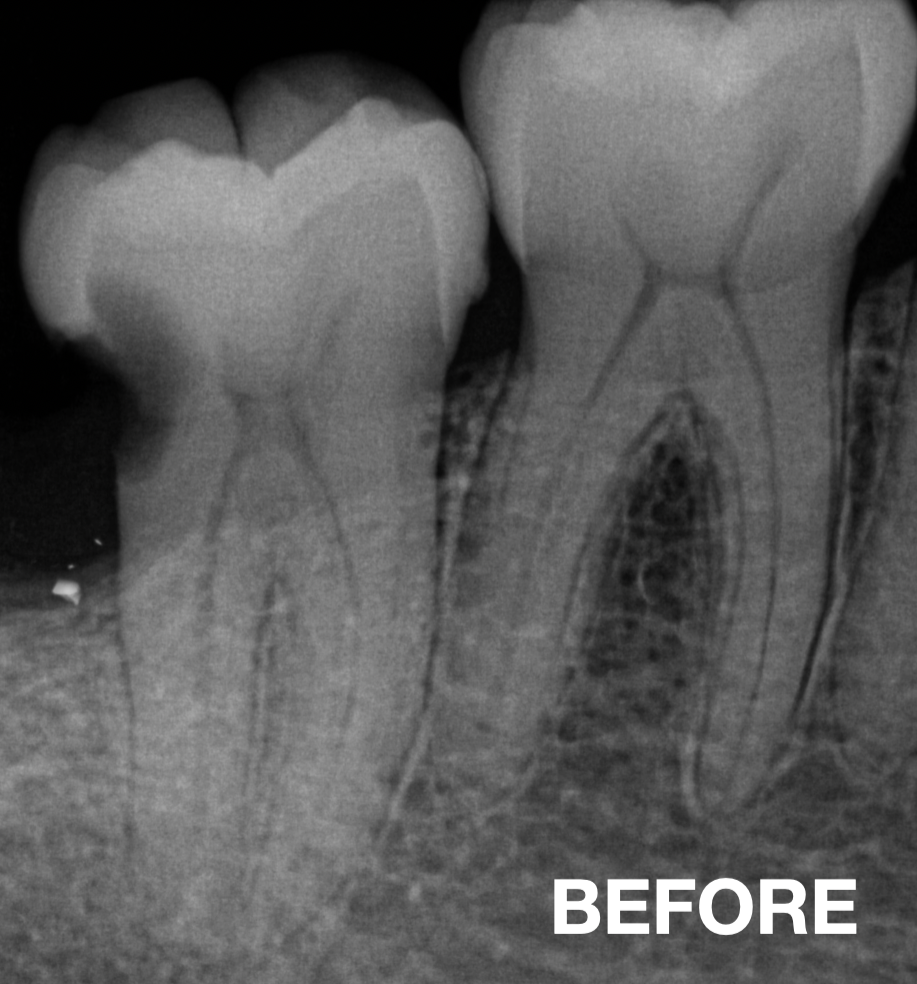

Before & After

📸 Before: missing tooth / fractured tooth

📸 After: restored tooth with natural-looking FRC